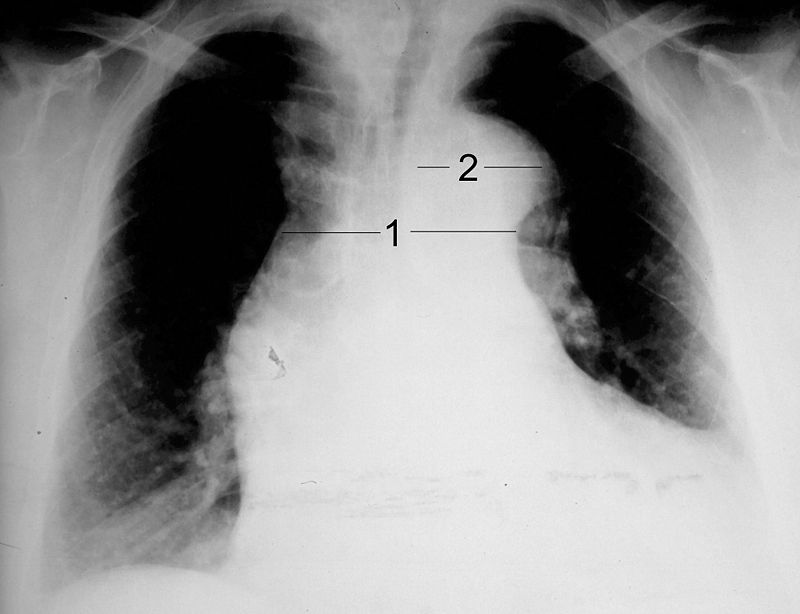

Thoracic Aneurysm

An aneurism of the thoracic aorta is a thoracic aneurysm.

Thoracic aneurysm risk factors include:

- Syphilis

- Hypertension

Tertiary syphilis is a common cause of thoracic aneurysm.

Tertiary syphilis can cause vasa vasorum endarteritis leading to thoracic aneurysm due to:

- Luminal constriction

- Reduced blood flow

- Vascular wall atrophy

Tertiary syphilis results in the aorta having a “tree-bark” look.

Complications of thoracic aneurysm includes:

- Airway compression

- Esophagus compression

- Thrombosis

- Embolism

Abdominal Aortic Aneurysm

Abdominal aortic aneurysm (AAA) is an aneurysm of the abdominal aorta.

Abdominal aortic aneurysm typically develops above the aortic bifurcation but below the renal arteries.

Abdominal aortic aneurysm (AAA) is typically associated with hypertension and atherosclerosis.